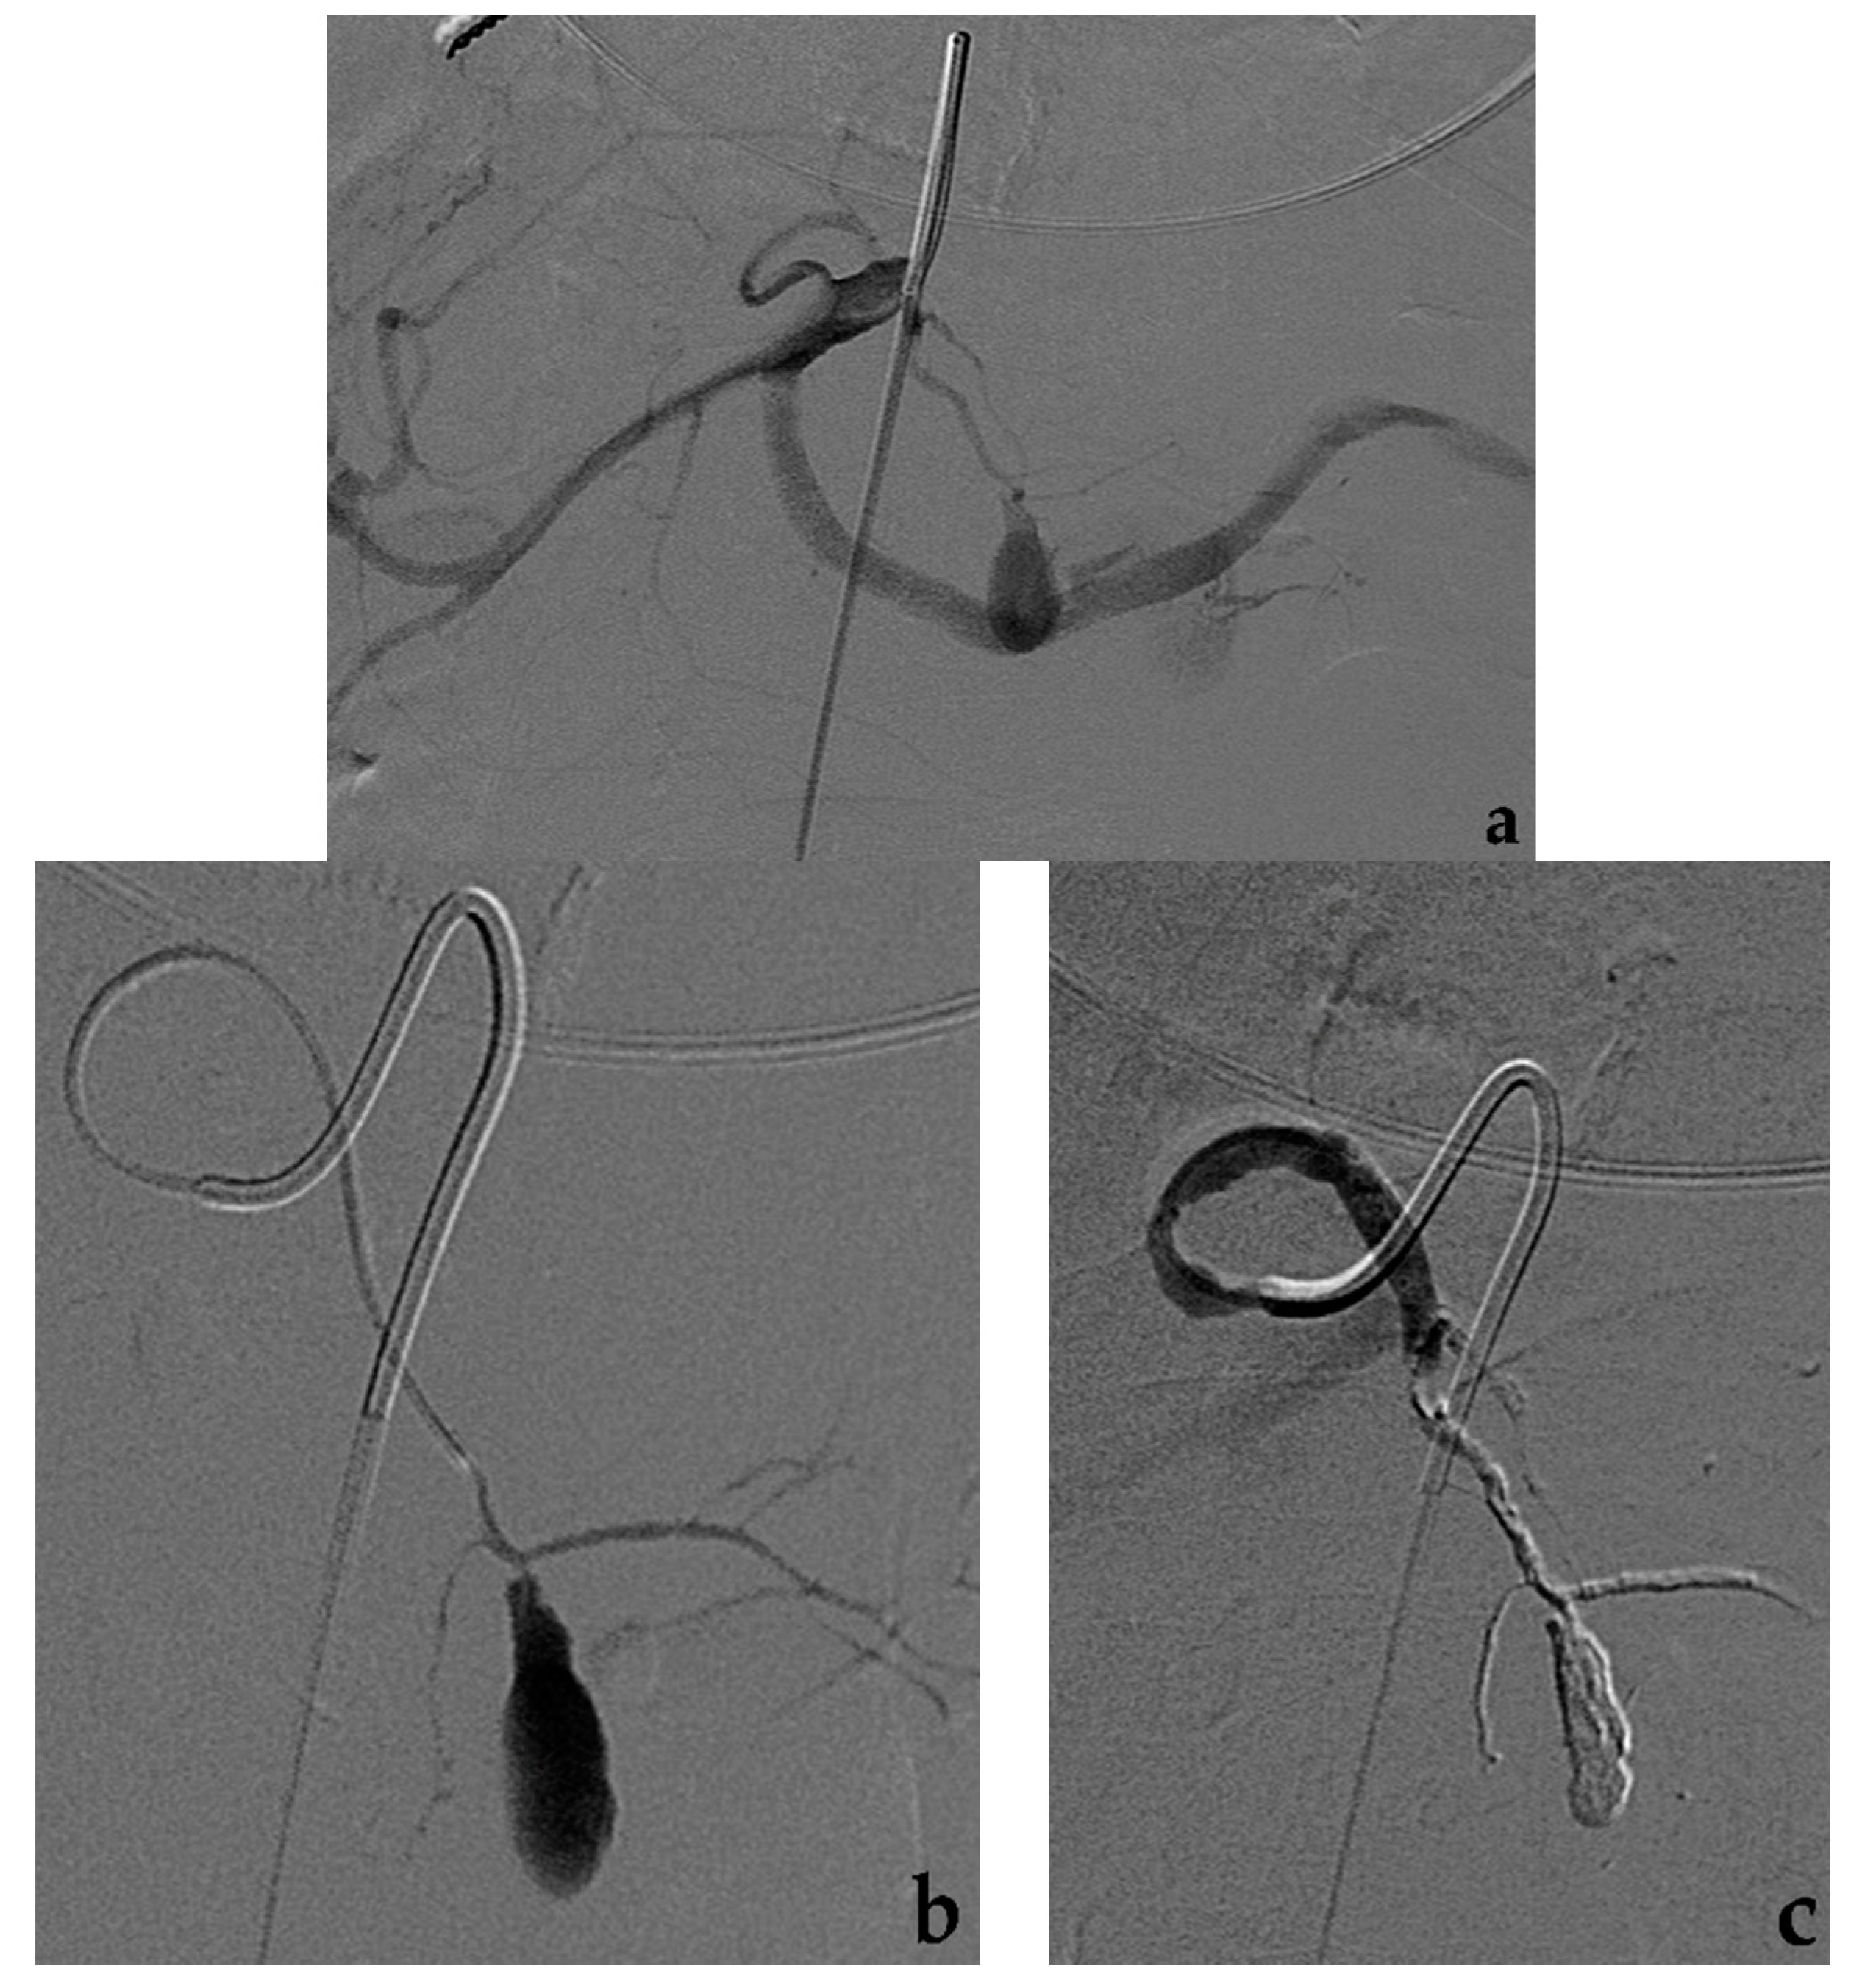

6. Percutaneous (or Endoscopic) Approach

- Piffaretti, G.; Tozzi, M.; Carrafiello, G.; Caronno, R.; Laganà, D.; Recaldini, C.; Castelli, P. A case of gastroduodenal artery aneurysm in a HIV-positive patient treated by combined percutaneous thrombin injection and endovascular coil embolization. J. Cardiovasc. Surg. 2008, 49, 659–661. [Google Scholar]

- Gorsi, U.; Agarwal, V.; Nair, V.; Kang, M.; Kalra, N.; Sreedhara, B.C.; Gupta, R.; Rana, S.S.; Dutta, U.; Sandhu, M.S. Endovascular and percutaneous transabdominal embolisation of pseudoaneurysms in pancreatitis: An experience from a tertiary-care referral centre. Clin. Radiol. 2021, 76, 314.e17–314.e23. [Google Scholar] [CrossRef]